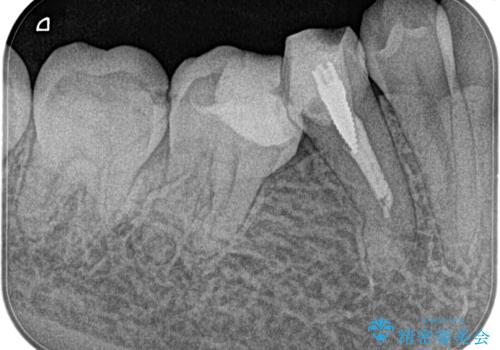

【湾曲根管】奥歯がズキズキ痛い

担当医 河口智英